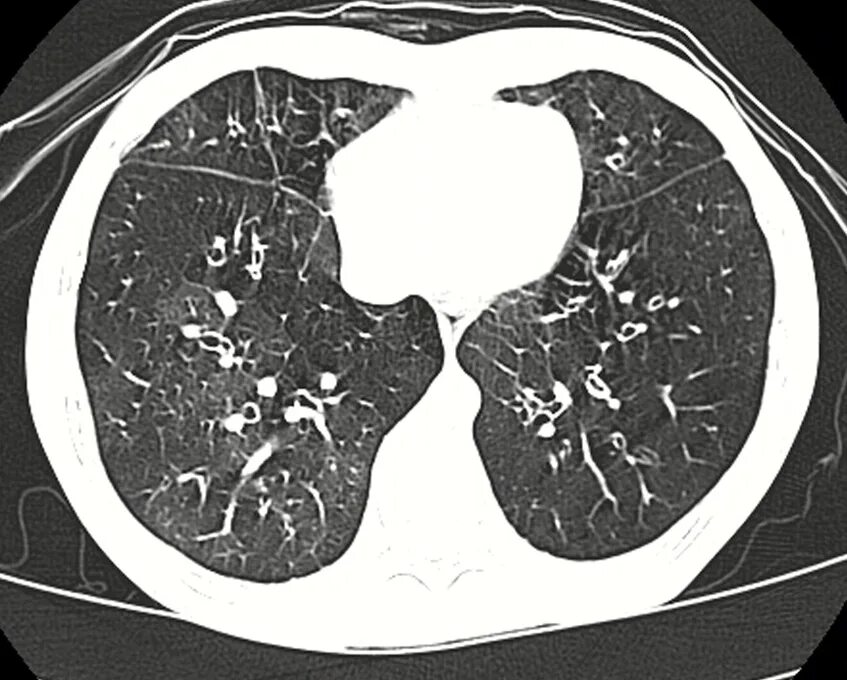

Утолщение бронха